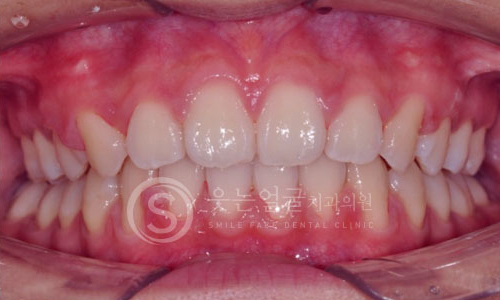

한눈에 보는

치아교정 전후사진